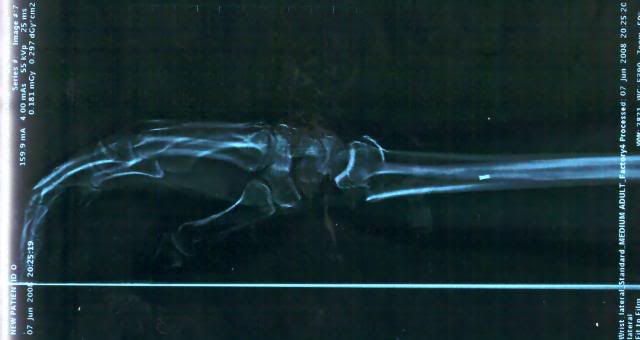

What up everyone? it's been a long time. Been very busy with the fam and getting back into everything. I just got home from a week in Wisconsin with DeCosters kids. I dislocated my good knee the first day and rode hurt the whole week. If you've picked up the last 3 issues of cycle news you've seen adds for DeCoster's kids in them. here are some pics from the show in Chile, and the x rays of my wrists when I broke them in Equador. I'm semi retireing from the pro scene, I'm tired of being gone all the time. I'm getting my personal trainers licence and going that route. I'll still do Decosters shows & local fmx demo's when I feel like it. Hope you all like the pics.

and the broken wrists